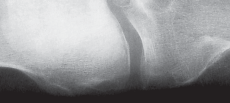

التصوير الطبي

التصوير الطبي ضروري لتأكيد التشخيص وتحديد مدى تلف المفصل:

-

الأشعة السينية العادية (Plain Radiographs):

- المنظر الأمامي الخلفي (AP): يُظهر الركبة من الأمام.

- المنظر الجانبي (Lateral): يُظهر الركبة من الجانب.

- المنظر الخلفي الأمامي المثني (PA Flexed): يسمح بتقييم أفضل للجزء الخلفي من الركبة وقد يكشف عن تغيرات أكبر في الحجرة الخلفية الوحشية.

- منظر شروق الشمس (Sunrise/Patellofemoral): لتقييم المفصل الرضفي الفخذي.

- الأشعة السينية الطويلة للطرف السفلي بالكامل (Full-length standing radiographs): من الورك إلى الكاحل، وهي مفيدة جدًا، خاصة إذا تم استخدام تقنيات الملاحة الحاسوبية. تُظهر هذه الأشعة المحاذاة الكلية للطرف السفلي.